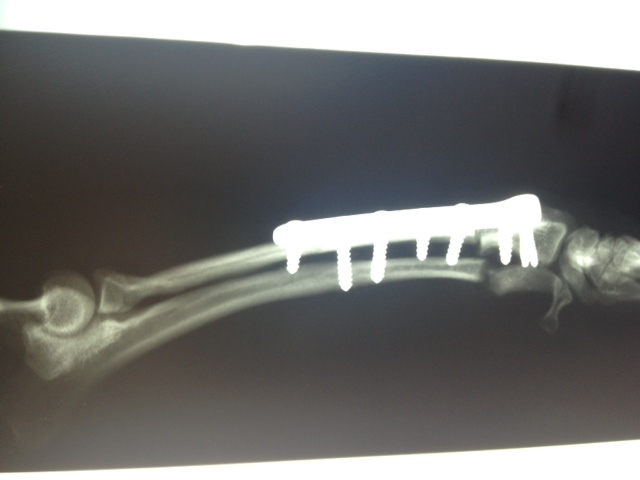

Wir waren alle sehr aufgeregt. Und selbst der erfahrene Arzt meinte, es sei eine ungewöhnliche Aktion, denn normalerweise weist nur ein Pfötchen so starke Anomalien auf. Er hatte es noch nicht, dass beide operiert werden müssen.

In sechs Wochen erfolgt dann die zweite OP.